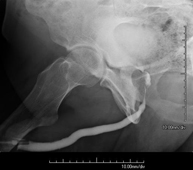

Técnica mediante la cual, utilizando rayos X, se obtienen imágenes del interior de las extremidades para su estudio, especialmente de los huesos. Indicaciones: traumatismo, infecciones articulares. - RX Artrografía

Procedimiento que permite, mediante el uso de rayos X, y tras inyectar un contraste en el interior de la articulación, detectar lesiones de determinadas articulaciones (cartílago, hueso, tendones, etc.) según la distribución del contraste. - RX Pelvis

Estudio que, utilizando los rayos X, permite obtener una imagen de los huesos de la cadera y descartar luxaciones. - RX Seriada ósea

Estudio que, utilizando los rayos X, permite obtener una imagen de los huesos de la cadera y descartar luxaciones. - Cistografía